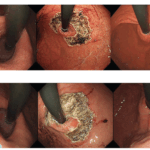

FRONTIERS IN ENDOSCOPY, SERIES #102

Electrohydraulic Lithotripsy for Biliary and Pancreatic Stones

Electrohydraulic lithotripsy (EHL) has emerged as a vital adjunct to endoscopic retrograde cholangiopancreatography (ERCP), providing an effective means of fragmenting large, impacted, or otherwise difficult-to-extract stones within the pancreatic and […]